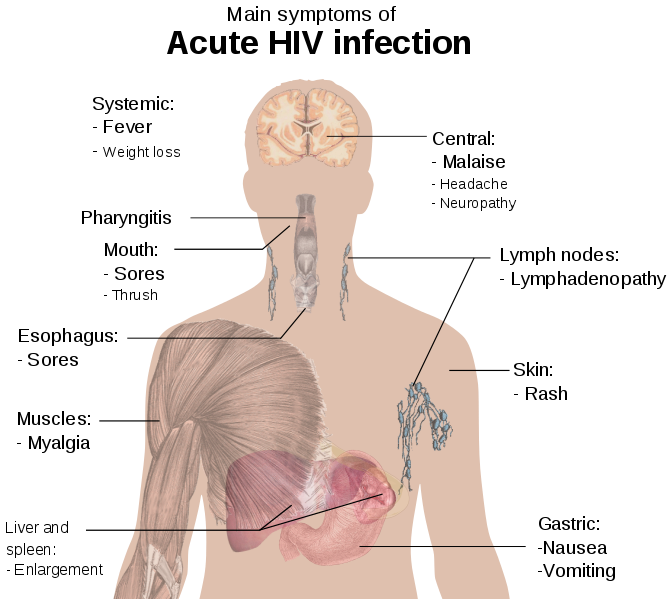

These are some of the most common symptoms of HIV